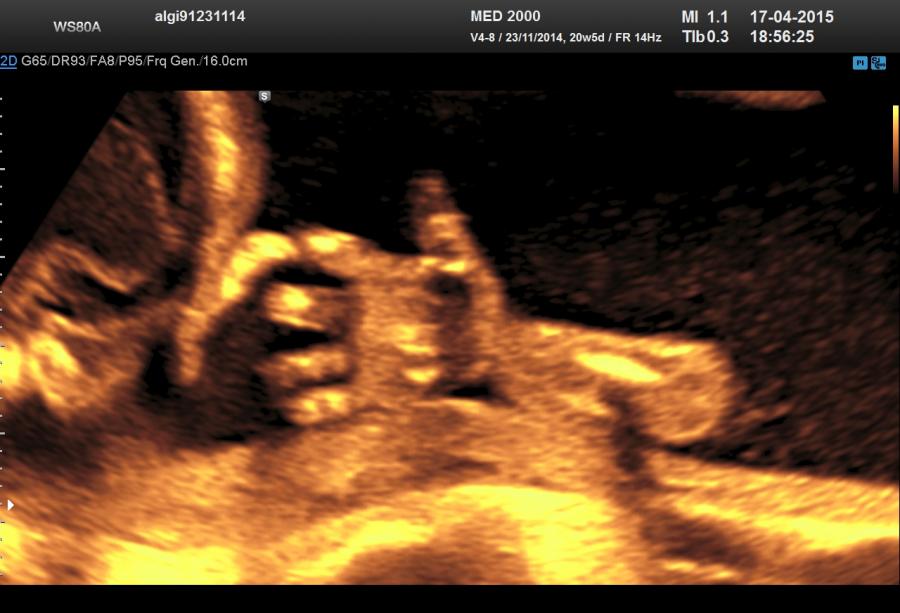

Le alterazioni a carico del tratto acromelico (di difficile o impossibile riconoscimento ecografico) consistono in polidattilia (preassiale, postassiale), sindattilia, clinodattilia, ectrodattilia, campodattilia.

Lo studio del tratto acromelico rappresenta un valido aiuto nella definizione delle varie displasie scheletriche per la frequente associazione tra tipo di anomalia del segmento acromelico e varie displasie. Tali patologie sono appresso elencate:

Polidatilia - viene distinta in:

Polidattilia preassiale se le dita sovrannumerarie sono localizzate al lato radiale per l'arto superiore e tibiale per l'arto inferiore (praticamente il dito sovrannumerario è contiguo al I dito).

Polidattilia postassiale se le dita sovrannumerarie sono localizzate al lato ulnare per l'arto superiore e fibulare per l'arto inferiore (praticamente il dito sovrannumerario è contiguo al V dito).